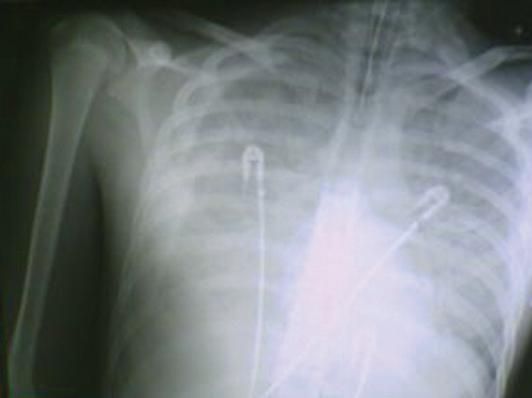

Chest radiographs, obtained daily, showed diffuse bilateral alveolointerstitial infiltrates (Figure 1); a moderate bilateral pleural effusion occurred during the second week of hospitalization (Figure 2).

Figure 2 - The extensive lesions shown here are responsible for the patient's acute respiratorydistress syndrome. Pleural effusion is most prominent on the right side of the chest.